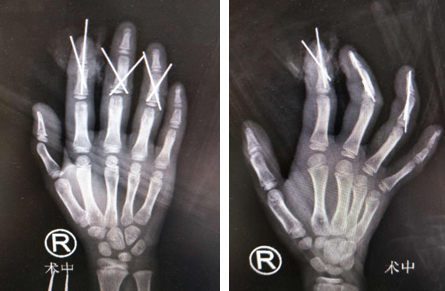

医院总值班迅速为小女孩开通绿色通道,手外科一病区李甲、滕道练、钱军医生手术团队为其进行了“右手示中环小指清创骨折复位内固定血管神经肌腱修复术+血管移植术+小指原位回植术”。术中清除右示中环小指伤口污染失活组织,探查见右示指自远节指骨基底部离断,累及远节指间关节面,中环指中节指骨头体部及以远完全离断,小指自甲根部以远完全离断,于十倍显微镜下吻合动静脉及神经,血管通血良好。

目前小女孩恢复情况良好,示中环三指指体已成活,小指正在进一步的观察恢复中。